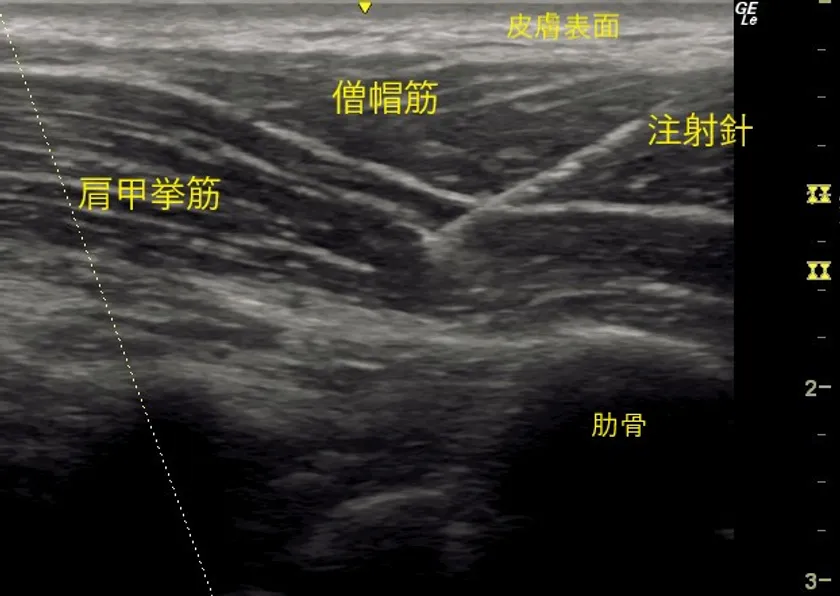

僧帽筋の奥にある肩甲挙筋に針が刺入

首肩では筋層がいくつか重なっています。

一般的な肩こりでは、中間層、もしくはより深層の筋肉に負担がかかっているという問題が存在します。

いずれにしても首肩こりの多くは、奥の方の筋肉にトラブルが見受けられます。

そこで中間層、深層まで針を入れて薬液注入する必要があるのですが、エコー等を見ないとどこに入っているか分かりません。

また、ブラインドで注射すると大血管や、肺、神経などに刺してしまう危険が増大します。

首肩こりにおいて、筋肉のどこに負担がかかっているのかエコーで見つけることができます。

当院では、首肩こりの患者さんにどの辺りがこっているかを伺い、その該当する筋肉をエコーで調べ負担のかかっている箇所の筋腹に確実にボトックス注射をすることになります。